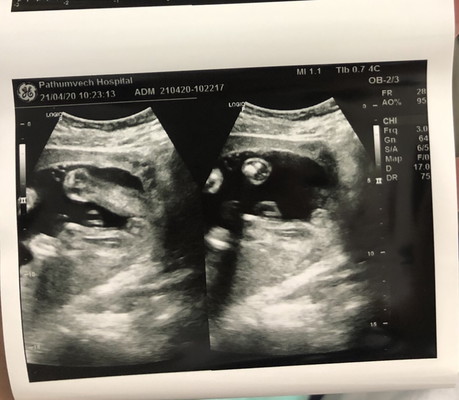

24 วีคแล้วค่ะ

คุณหมอซาวด์แล้วบอกว่าได้ลูกสาว เป็นไปได้มั้ยคะที่จะเป็นผช.ตอนคลอด เพราะพี่ที่ทำงานเคยเจอกรณีแบบนี้ ตอนซาวได้ผญ พอคลอดได้ ผช เลยแอบกังวลนิดหน่อยค่ะ

แต่รูปซาวด์ของแม่ชัดอยุ่นะคะ และน้องอ้าขาเต็มที่เลย มีโอกาสค่ะแต่เราว่าก็ไม่ใช่ว่าจะบ่อย เว้นแล้วน้องหนีบๆดูไม่ชัด

ญ.ชัวร์ค่ะ รูปชัด เพราะรูปแรกตรงหว่างขาเป็นแคม ไม่มีเจดีย์งอกออกมา

ถ้าเห็นชัด ก็ไม่ต้องกลัวคะ แต่ถ้าเห็นแบบไม่เต็มอาจจะมีสิทเปลี่ยน